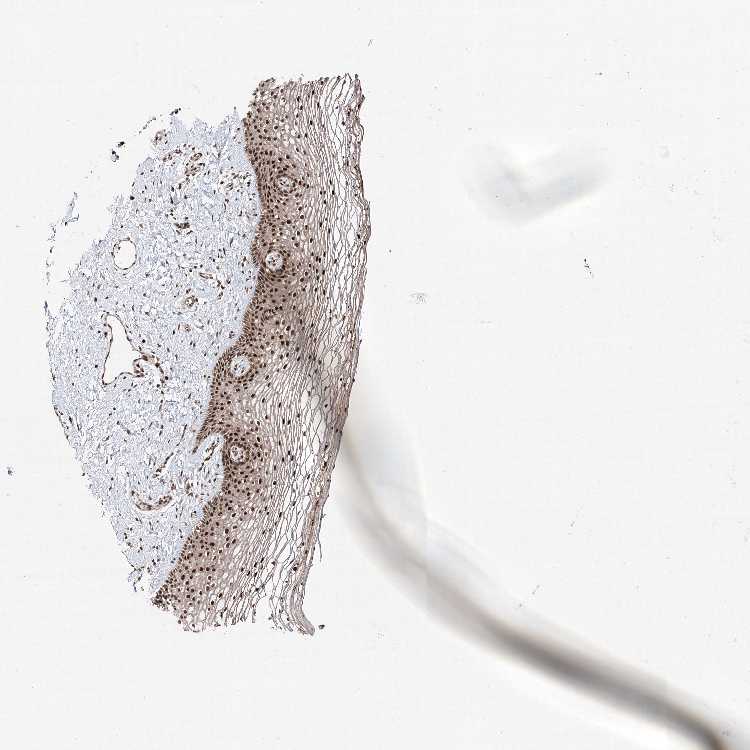

TISSUE PRIMARY DATA VAGINA Show tissue menu

VAGINA - Antibody stainingi

Antibody staining in the annotated cell types in the current human tissue is reported as not detected, low, medium, or high, based on conventional immunohistochemistry profiling in selected tissues. This score is based on the combination of the staining intensity and fraction of stained cells.

Each image is clickable and will lead to virtual microscopy that enables deeper exploration of all samples and also displays staining intensity scores, fraction scores and subcellular localization as well as patient and tissue information for each sample.

Antibody HPA001032Antibody HPA027214Antibody CAB037024

Squamous epithelial cells HighHighHigh